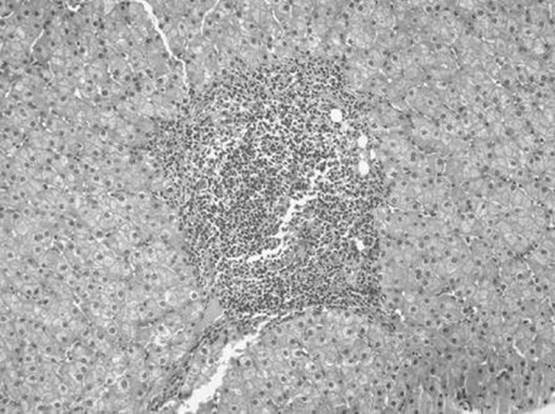

The liver biopsy specimen shown in the figure below is described in the pathology report as having nodular lymphocytic portal infiltrates, some with germinal centers. This is most suggestive of what type of viral hepatitis?

Figure 51-4

Hepatitis C. The presence of a portal area with a lymphoid aggregate or a follicle with a germinal center in a liver specimen with other features of chronic hepatitis is most suggestive of chronic hepatitis C. It should be noted that hepatitis C is notable for sometimes having some degree of bile duct involvement/injury. This can make the distinction between recurrent hepatitis C and allograft rejection difficult in some liver transplant biopsies.